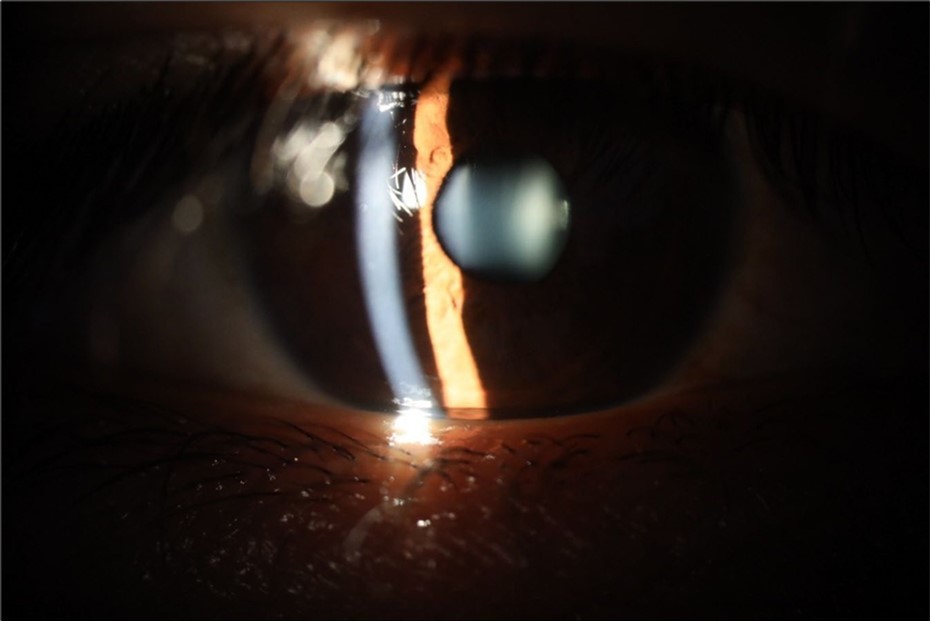

Figure 5.The slit-lamp photograph shows the anterior segment, relatively unscathed, in terms of transparent media (Cornea, crystalline and vitreous).

Figure 6.Slit-lamp examination showed a solution of continuity in the left temporal region, which fortunately only affected the conjunctiva and Tenon's capsule, while the sclera was unscathed.

Figure 15.The photograph shows better specular reflection, compared to the first day of the exam.

Figure 16.The anterior segment of the right eye shows the vitreous with greater transparency. The cornea and lens, as well as the anterior chamber, are in good condition.

Figure 25.Mirror reflection of the affected eye (right side), with good appearance. This indicates that the transparent media of the eyeball (Cornea, anterior chamber, lens, and vitreous) are in good condition.

Figure 26.The macrograph of the anterior segment of the right eye (affected) shows very good transparency of the cornea, anterior chamber, lens, and vitreous.

Figure 31.The photograph of the right eye shows an almost normal mirror reflection, as well as a better pupillary dilation.

Figure 32.The macro photograph of the right eye shows us a cornea, anterior camera, and crystalline lens in very good condition.